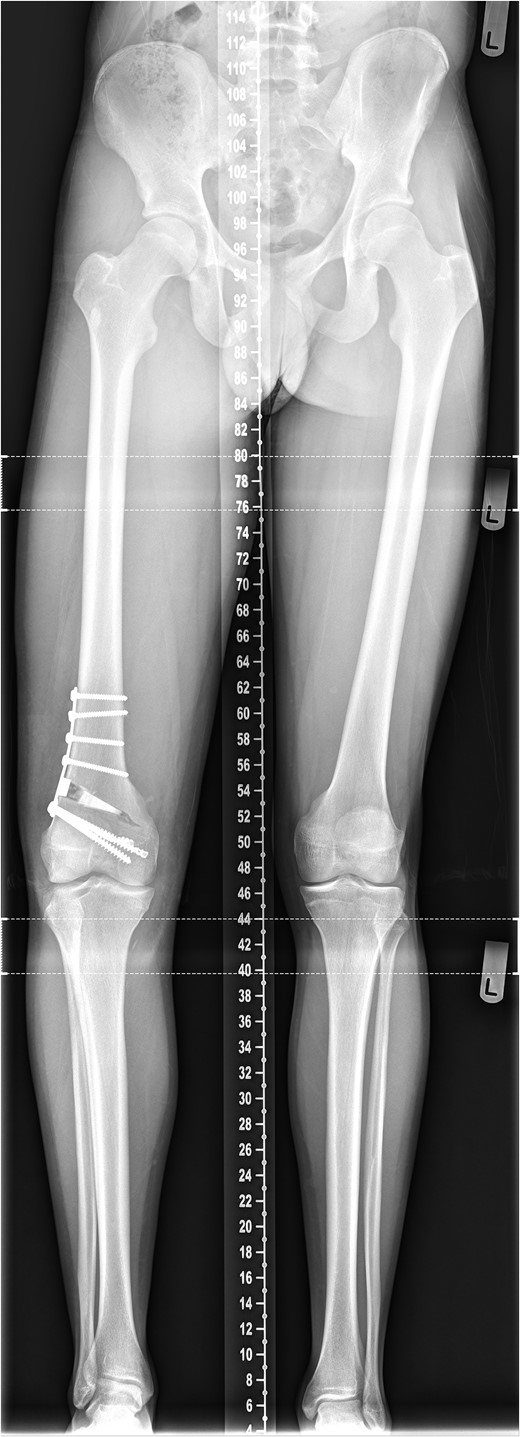

The patient's initial management was non-operative with a period of knee protection with a range of movement brace and intensive rehabilitation. Approximately 3 months after the index injury he returned to competitive football but shortly after his return sustained a further valgus injury and despite further conservative treatment was unable to return to sport. He was referred to our service with ongoing instability symptoms. Upon clinical assessment we noted an asymmetric valgus alignment of the knee and abnormal laxity of the MCL. Radiographic investigations revealed an abnormality of the lateral distal femur and alignment radiographs confirmed the valgus mal-alignment with abnormal opening of the medial tibio-femoral joint space on single-leg stance radiographs (Figs 2–4). We obtained the patient's MRI scan and reviewing this with Radiology colleagues revealed subtle changes of increased lateral femoral physis fluid density on T-2 weighted images consistent with a Salter Harris Type V injury (Fig. 5).

Radiograph demonstrating opening of the medial compartment and increased valgus alignment on single-limb weight bearing.